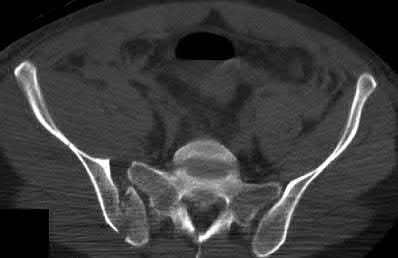

Which of the following images shows an injury pattern most consistent with a lateral compression type 3 pelvic ring injury?

Figure C is an axial CT scan of a lateral compression type 3 (LC3) pelvic ring injury.

Classically, LC3 injuries demonstrate an ipsilateral lateral compression and a contralateral APC (windswept pelvis) fracture pattern. The most common mechanism of injury in these cases is a rollover MVC or pedestrian vs. auto. LC1 injuries are characterized by an oblique or transverse ramus fracture and ipsilateral anterior sacral ala compression fracture, while LC2 injuries consist of a rami fracture and ipsilateral posterior ilium fracture dislocation (crescent fracture). While LC1 injuries can often initially be managed conservatively with protected weight-bearing and close observation, LC2 and LC3 pelvic ring injuries are almost universally operative.

Answer 1: This represents a lateral compression type 2 injury. Answer 2: This represents a lateral compression type 1 injury.

Answer 4: This represents an anterior posterior compression type 2 injury. Answer 5: This represents an anterior posterior compression type 3 injury.